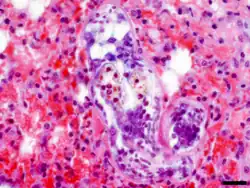

Infikované myši i ostatní zvířata (křečci, králíci, makakové rhesus) mají na povrchu plic četné hemoragie.[16][20] Při histopatologickém vyšetření je pozorováno překrvení a edémy plicní tkáně a 4. den po infekci také shlukování lymfocytů v okrajových částech plicních laloků.[16] Schistosomula T. szidati se v plicích myší nalézají nejdříve 10 h po infekci[19] a nejpozději 10. den po infekci.[16] S přihlédnutím na nepoškozený tegument je za jejich úhyn zodpovědný buď neznámý imunologický faktor, nebo nedostatek esenciálních nutričních látek.[22]